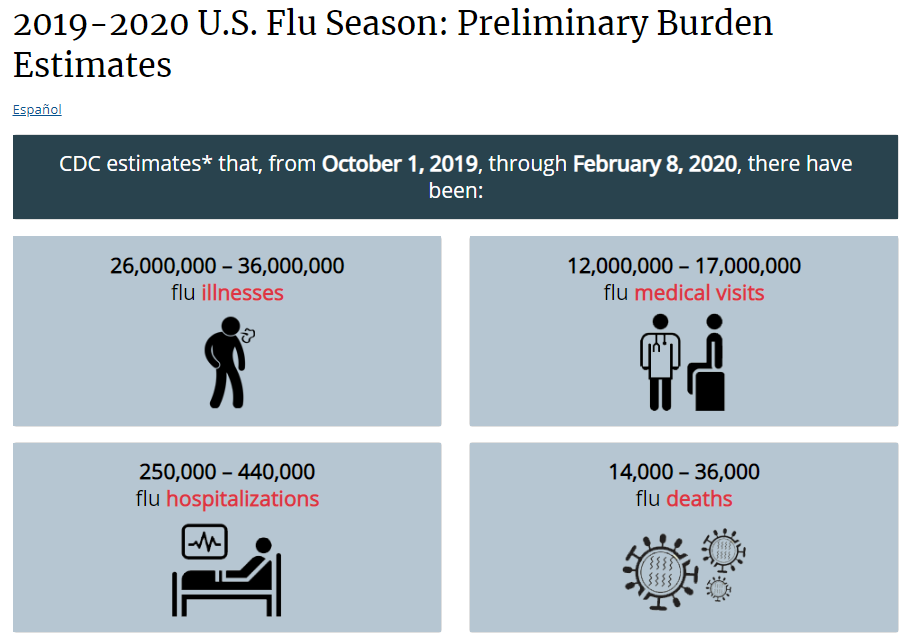

2020年是让人闻风丧胆的一年,这地狱般的开局里还有美国的流感。

据美国疾控中心CDC估计,自2019年流感季开始以来,到2020年2月8日。美国至少有

2600万人感染,其中有25万人需要住院治疗,14000人死亡(包括因并发症死亡的人数)。

除了美国本土各个地区都中招了,疫情甚至从美国扩散到了欧洲。

2019年11月至今年2月,法国已有26人死于流感,

疫情已在法国全境蔓延。

连俄罗斯也成了灾区,不少学校开始停课。